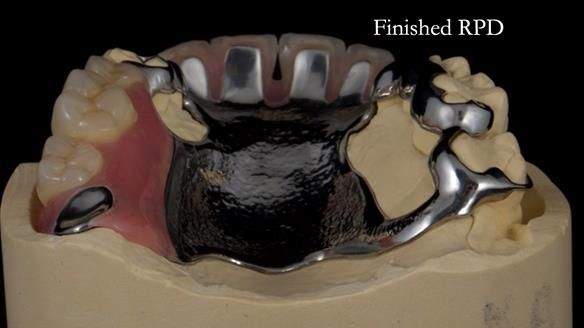

Keith’s case was one of the most challenging and rewarding cases I’ve treated this year. This 64 year old man presented with ill-fitting acrylic partial dentures that lacked stability, retention, and aesthetics. They constantly broke. He had lost the upper front teeth in a road traffic accident in his early 20s. The unopposed teeth had erupted, taking up space. After careful planning, we made a durable, metal-based upper partial denture/splint to address his dental concerns. He loved the outcome.

1. Denture design: A custom cobalt-chromium framework was Scandinavian-designed to maximise stability, protect the remaining teeth, and allow for future additions if needed.

4. Keith’s outcome: The final denture not only improved Keith’s bite, chewing function, and facial aesthetics but also protected his remaining teeth from further damage.

Keith’s denture incorporated a Duracetal shell clasp on upper right first premolar (Myerson), which are designed to be virtually visible, providing a more aesthetic solution while enhancing patient comfort. The Scandinavian-inspired approach, based in modern removable prosthodontic techniques, ensured the denture was not only durable but also visually pleasing. Additionally, the design was carefully planned to allow for future modifications, ensuring that if Keith loses additional teeth, the denture can be adapted rather than replaced entirely.